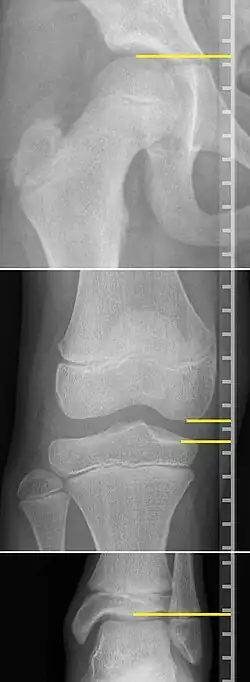

X-rays for leg length measurement.

On X-rays, there is generally measurement of both the femur and the tibia, as well as both combined.[4] Various measuring points for these have been suggested, but a functional method is to measure the distances between joint surfaces:[4]

• Femur length: The superior aspect of the femoral head and the distal portion of the medial femoral condyle.

• Tibial length: The medial tibial plateau and the tibial plafond

• Orthoroentgenogram, which takes separate images of the hip, knee and ankle.

On X-rays, the length of the lower limb can be measured from the proximal end of femoral head to the center of the plafond of the distal tibia.[13]